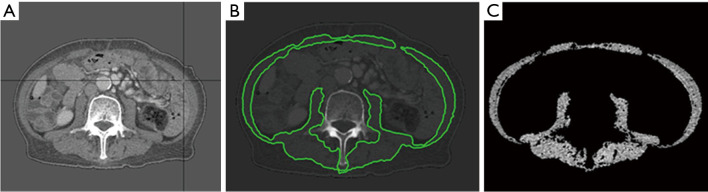

Methods: This study included patients with locally advanced ESCC who received CCRT without surgery between 2011-2020. Sarcopenia was assessed using the skeletal muscle index (SMI) at the third lumbar vertebra (L3), which includes the psoas, paraspinal, and abdominal wall muscles, based on cross-sectional computed tomography (CT) scans before and after CCRT.